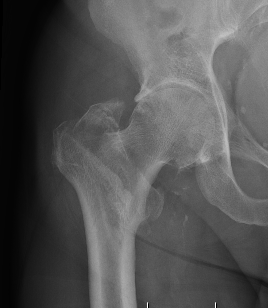

Definition

Fracture which extends between the trochanters of the proximal femur

Extra capsular / well vascularized

Evans Classification

Two main types

- Type 1 Intertrochanteric

- Type 2 Reverse Oblique

Type 1 Intertrochanteric

2 part undisplaced

2 part displaced

3 part without posterolateral support (GT fracture)

3 part without posteromedial support (LT fracture)

4 part without posterolateral or posteromedial support